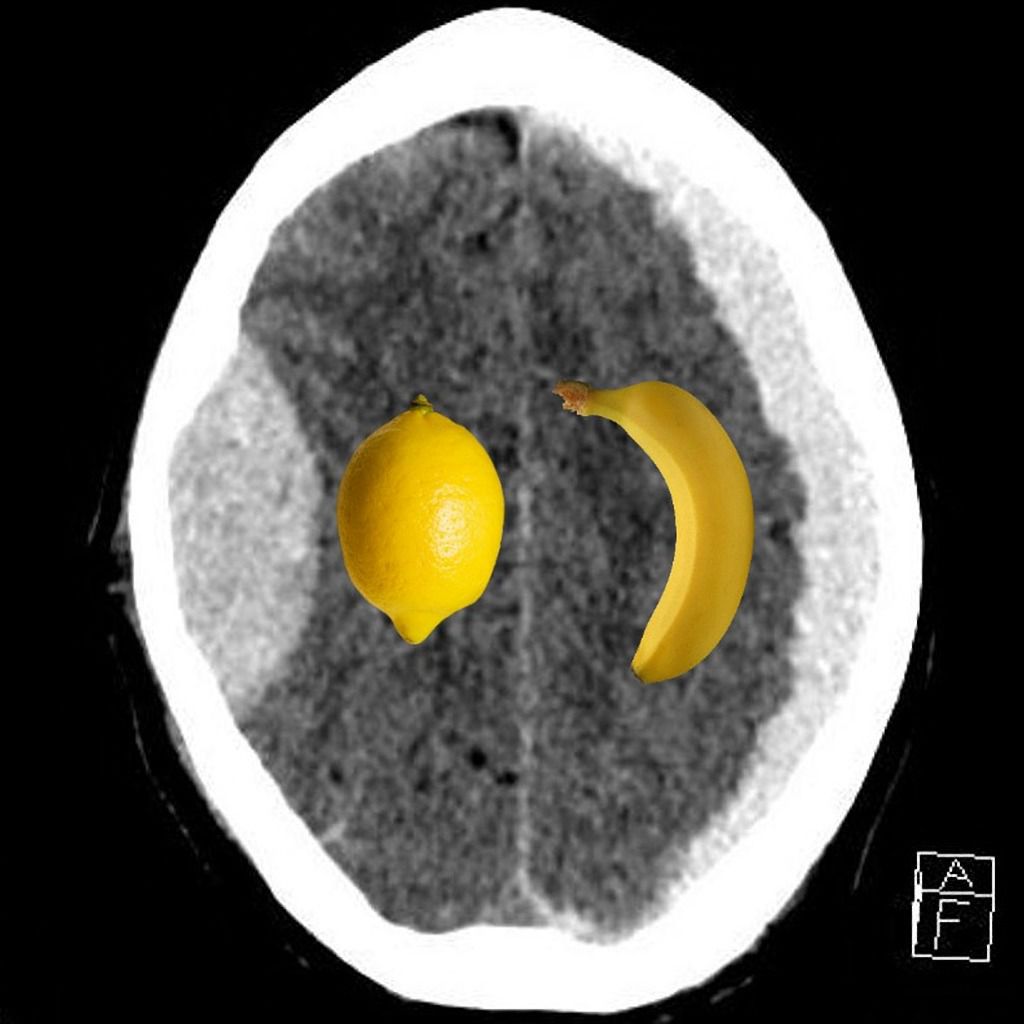

Extradural hematoma refers to accumulation of blood between skull bone and the dura mater. It appears as biconvex hyperintense lesion on CT scan. Subdural hematoma refers to bleeding between dura and arachnoid mater. On CT, the condition is identified as 'banana-shaped' hyperintense concave lesion. Reference: https://radiopaedia.org/cases/extradural-vs-subdural-haematoma-lemon-vs-banana Image via: https://radiopaedia.org/cases/extradural-vs-subdural-haematoma-lemon-vs-banana